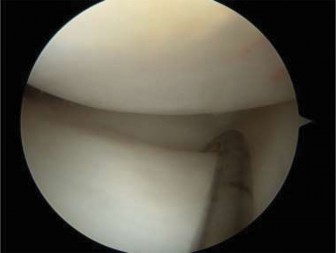

Figure 10–31

Figure 10–32

Discussion

The correct answer is (C). The arthroscopic images demonstrate a complete discoid meniscus which is covering the entire lateral tibial plateau. As the patient is symptomatic from the meniscus, saucerization is the first step in management. The meniscus is trimmed back using a combination of shavers and biters to a stable peripheral rim, which replicates the width of the native meniscus. Complete meniscectomy would not be indicated in a patient of this age due to the high risk of early onset degenerative arthritis. In fact, even prior to intervention, many discoid menisci have been associated with the development of lateral hemijoint osteochondral lesions. Although chondroplasty may be necessary, the meniscus is the underlying problem causing chondral wear and must be dealt with first. After saucerization is performed, the meniscus is probed and the following arthroscopic image is seen (Fig. 10–33). The next step in management is: